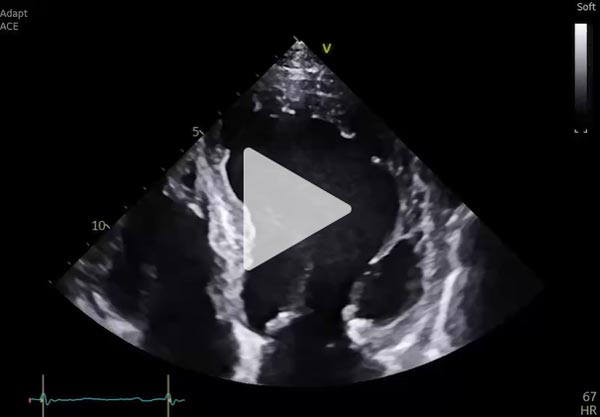

ETT de contrôle après cardioversion à USIC

- VG dilaté ( DTD 65 mm VTD 89 ml/m² ), hypertrophié ( SIV 14 mm PP 11 mm ),

- FEVG 33% en SP, hypokinésie diffuse plus marquée en antérieur et antérolatéral

- Débit cardiaque modérément abaissé

- IM modérée stable, pas de valvulopathie aortique significative

- Cavités droites dilatées normokinétiques

- PAPS 42 mmHg et POD 5mmHg

- Péricarde sec

Vidéo 1